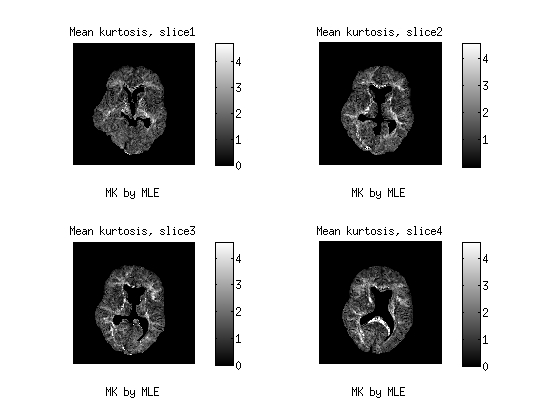

In this session, we depict the results by MD Fig. 3, FA Fig. 4 as well as MK Fig. 5 from the proposed CWLS and MLE methods.The diffusion weighted MR data is in the range of (0, 581), acquired by 32 distinct gradient directions with seven different b values. After comparison, we can see that the image constrasts by the MLE method gain much more detailed structural information, especially in Fig.4 and Fig. 5 than those by the CWLS in the same scales.

![[Uncaptioned image]](/html/1507.06780/assets/MK_cwls.jpg)

a

b